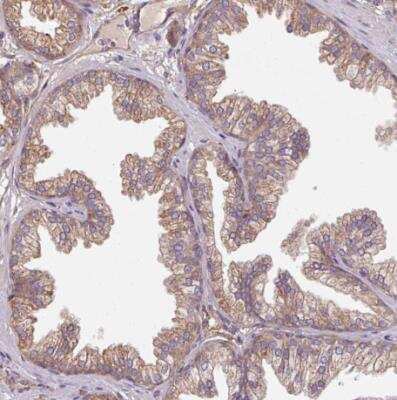

Immunohistochemistry-Paraffin: FAT4 Antibody [NBP2-49064] - Staining of human parathyroid gland shows moderate positivity in glandular cells.Immunohistochemistry-Paraffin: FAT4 Antibody [NBP2-49064]